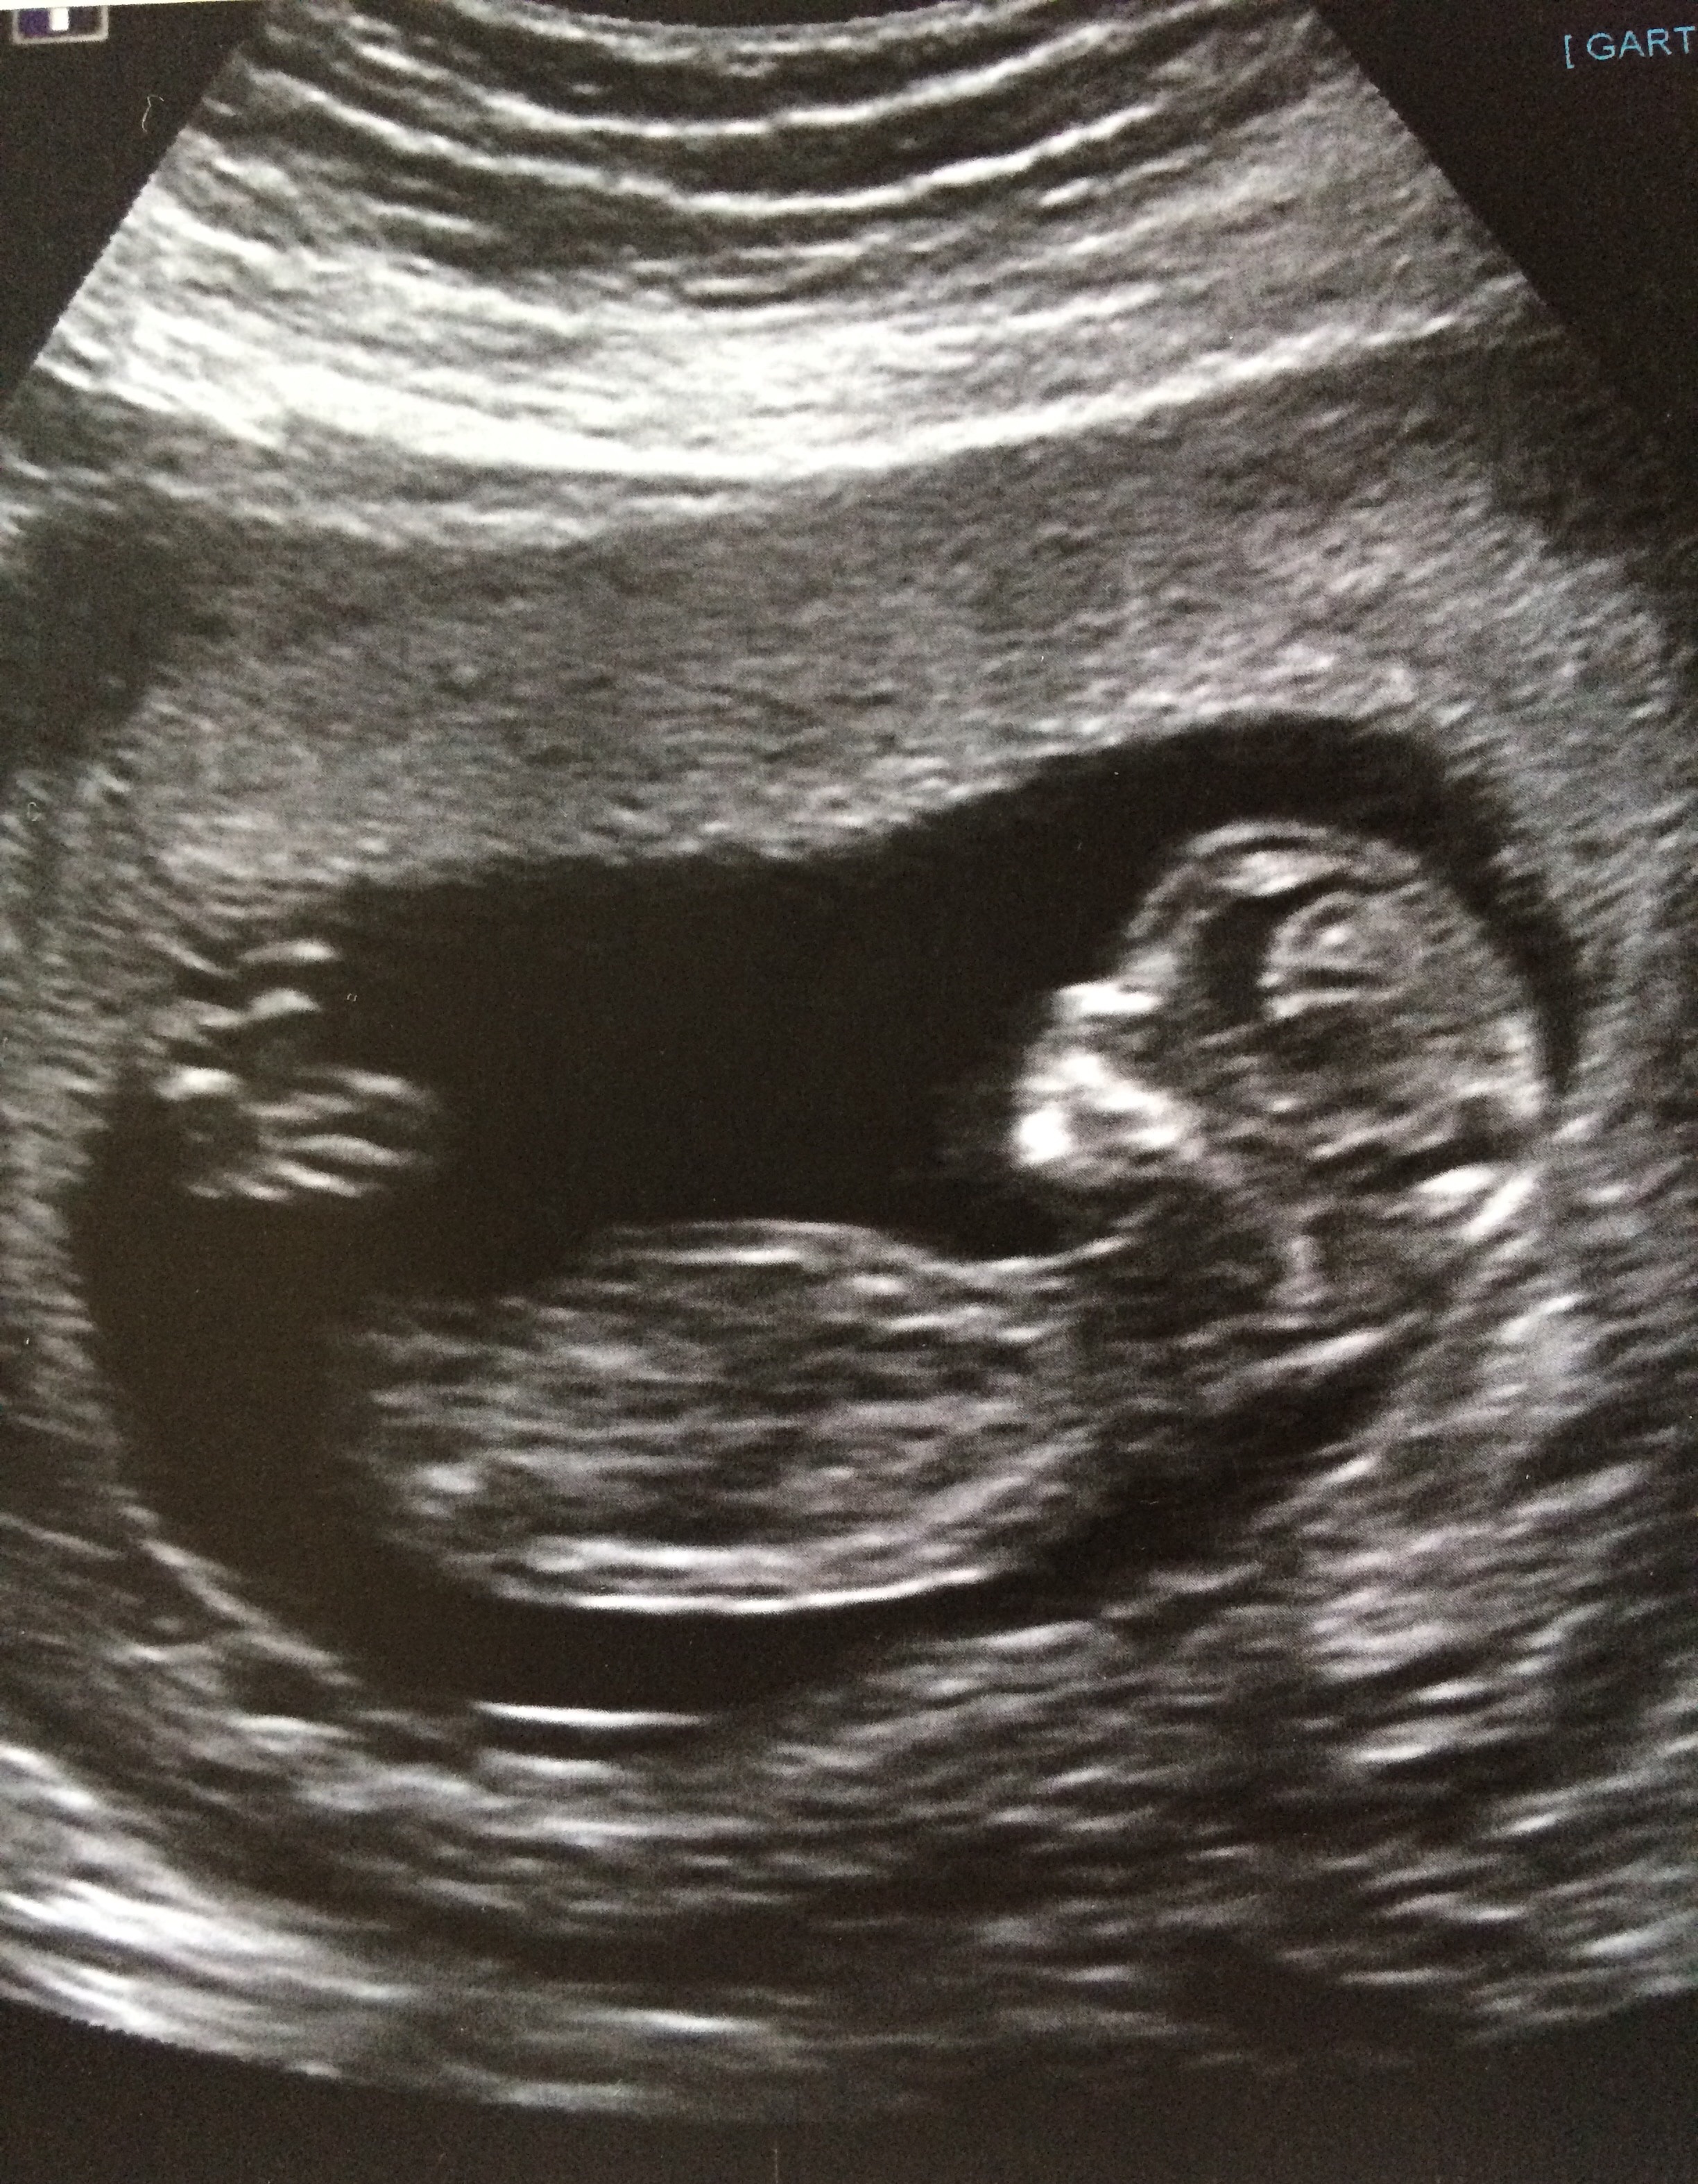

12 week ultra sound

I'd guess girl off first picture

I don't see a nub

girl lean